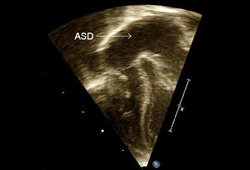

Tricuspid stenosis

Congenital tricuspid valve stenosis: 2D transthoracic echocardiogram apical 4 chamber view reveals a small tricuspid valve annulus (dash), RV hypoplasia, and a large atrial septal defect (ASD, arrow)

From the personal collection of Martin Bocks; used with permission